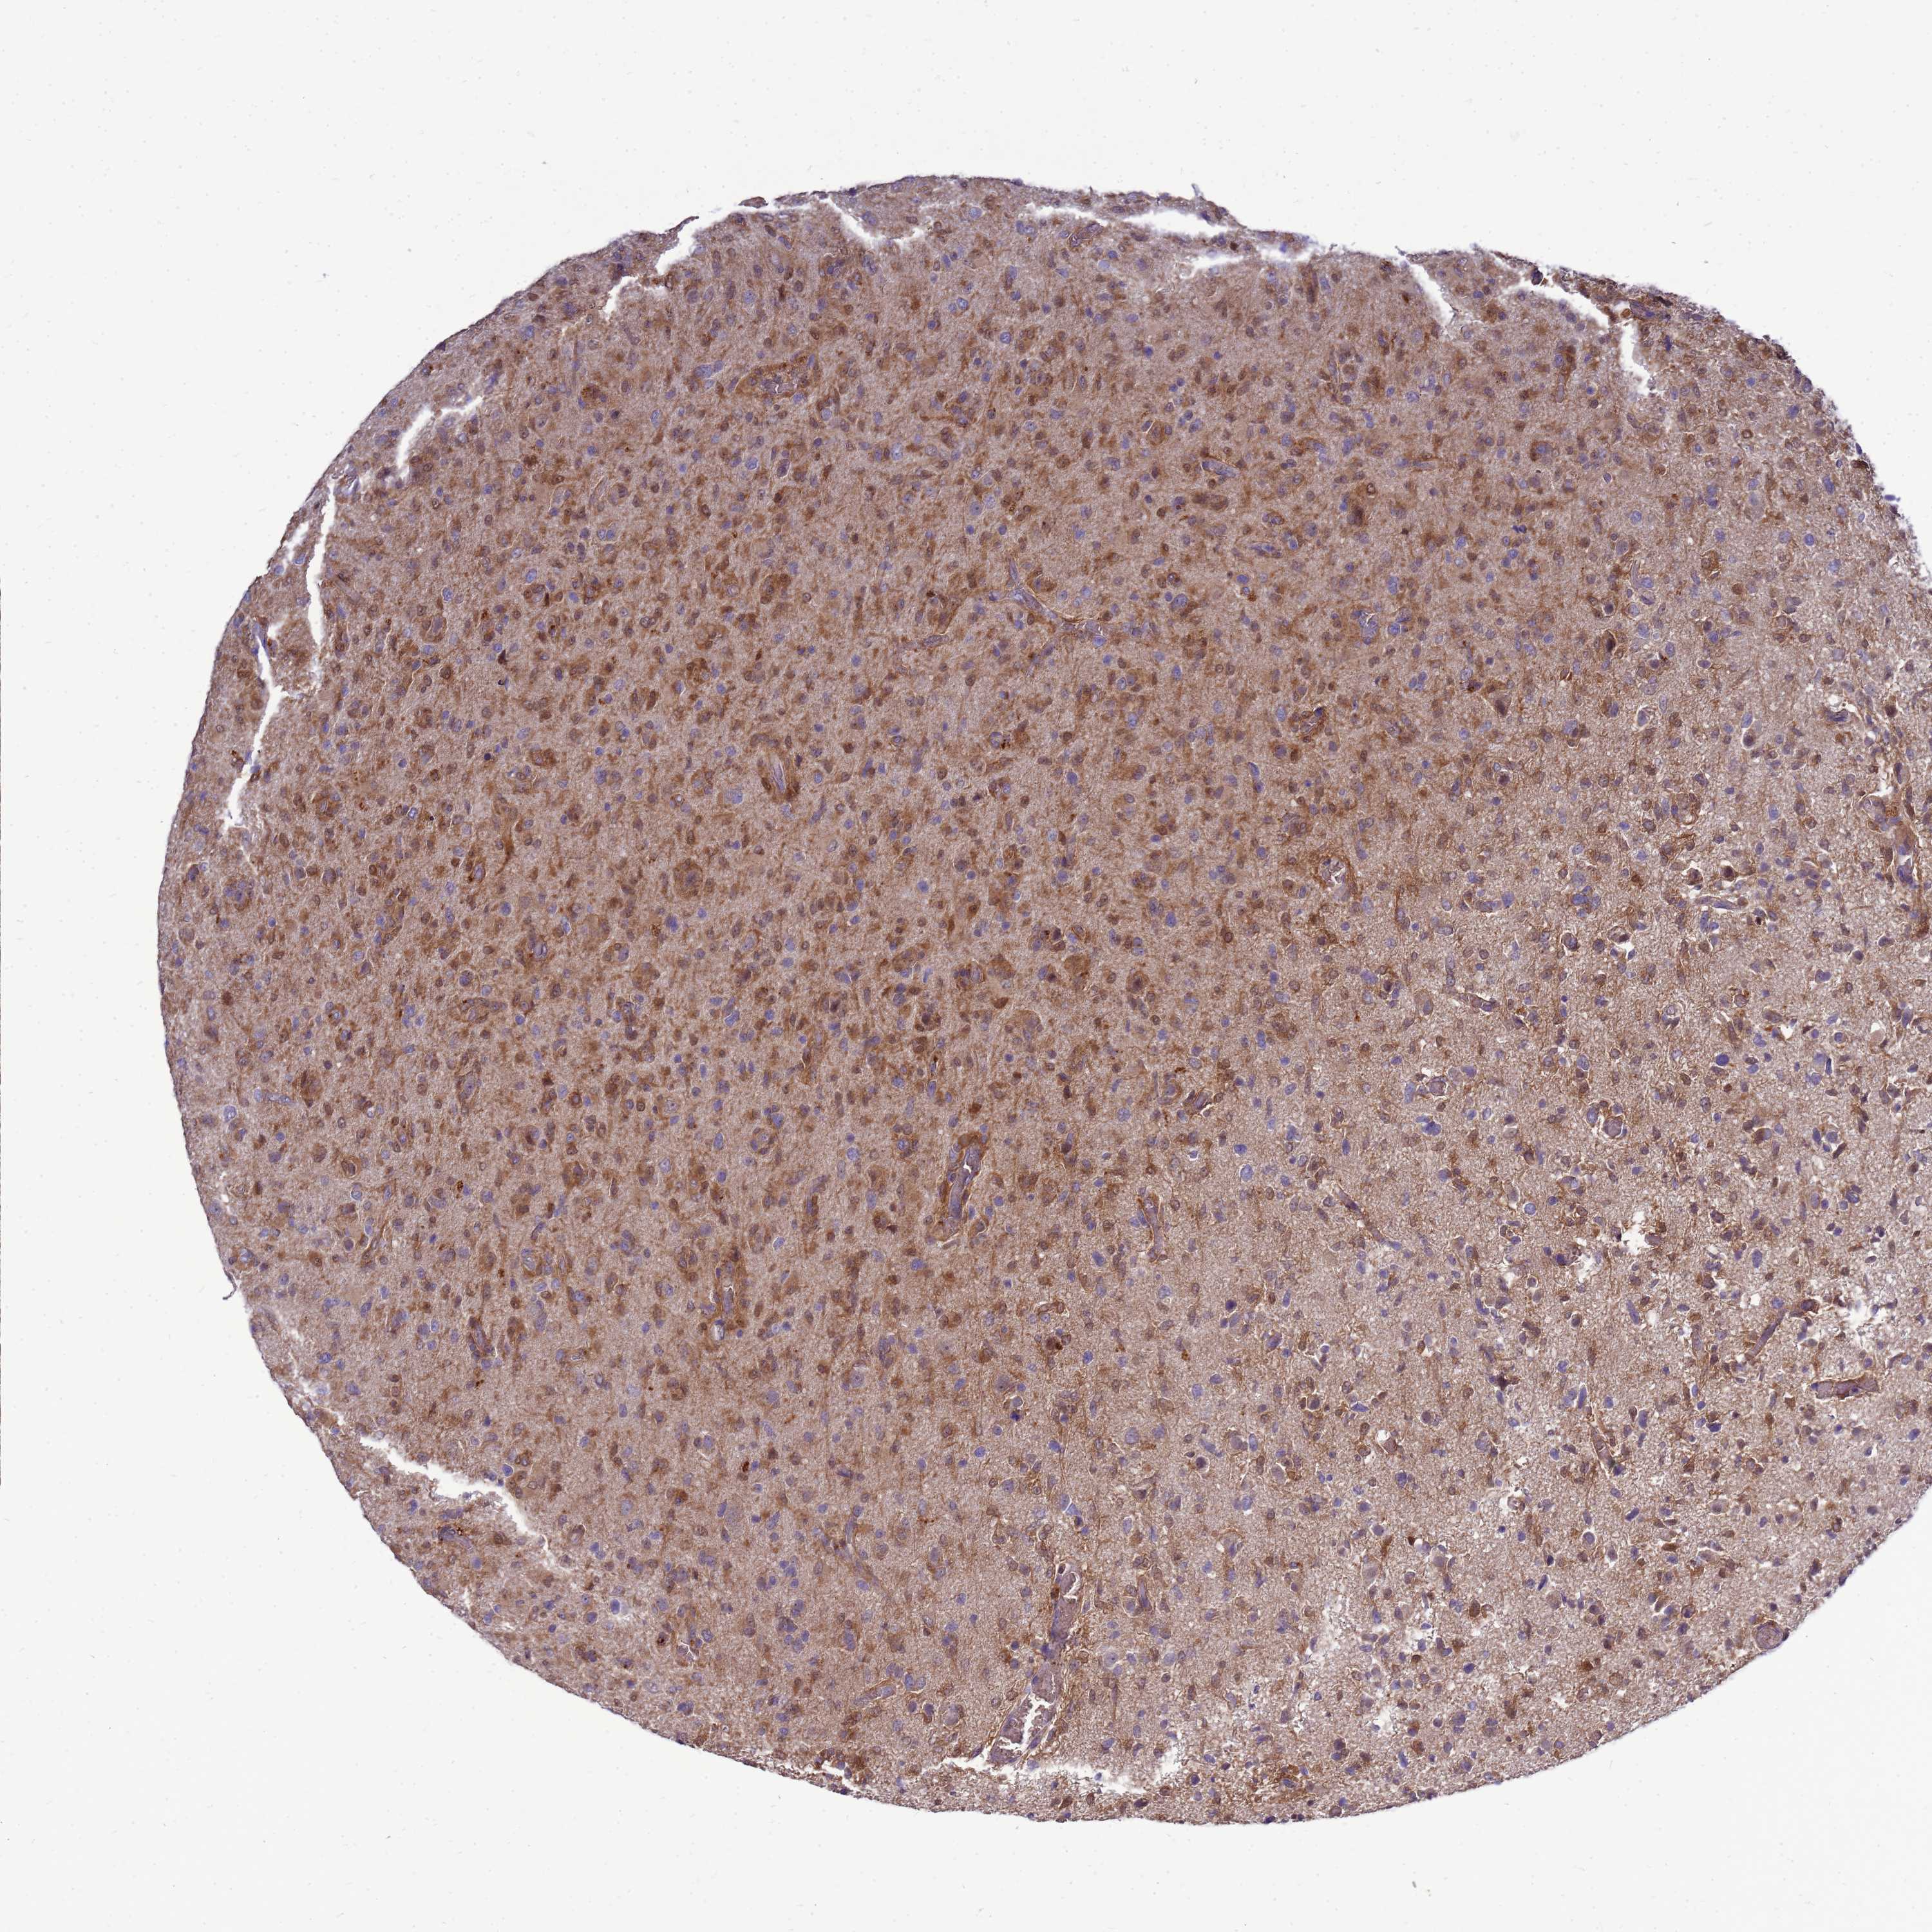

GLIOMA - Protein expressioni

A mouse-over function shows sample information and annotation data. Click on an image to view it in a full screen mode. Samples can be filtered based on level of antibody staining by selecting one or several of the following categories: high, medium, low and not detected. The assay and annotation is described here.

Note that samples used for immunohistochemistry by the Human Protein Atlas do not correspond to samples in the TCGA dataset.

Antibody stainingi

Antibody staining in the annotated cell types in the current human tissue is reported as not detected, low, medium, or high, based on conventional immunohistochemistry profiling in selected tissues. This score is based on the combination of the staining intensity and fraction of stained cells.

Each image is clickable and will lead to virtual microscopy that enables deeper exploration of all samples and also displays staining intensity scores, fraction scores and subcellular localization as well as patient and tissue information for each sample.

Antibody HPA045537

Staining

High

Medium

Low

Not detected

Intensity

Strong

Moderate

Weak

Negative

Quantity

>75%

75%-25%

<25%

None

Location

Nuclear

Cytoplasmic/membranous

Cytoplasmic/membranous,nuclear

Glioma, malignant, Low grade

Glioma, malignant, High grade

Glioblastoma, NOS